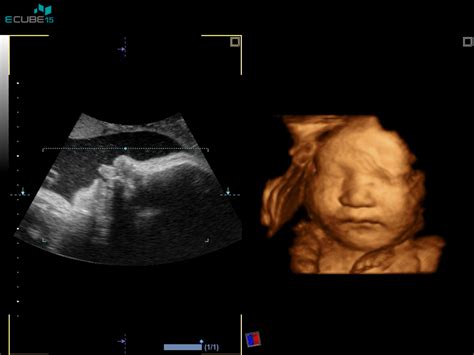

- UZ potrditev nosečnosti do 11. tedna.

- Pregled nuhalne svetline in dvojnega hormonskega testa med 11. in 14. tednom.

- Ultrazvočni pregled morfologije ploda v 20. tednu.

- UZ-nuhalna svetlina (11.-14. teden): Nuhalna svetlina z zgodnjo morfologijo ploda.

- UZ-morfologija (20.-23. teden): Morfologija ploda, rast, posteljica, plodovnica; laboratorijsko Hmg in toksoplazmoza.